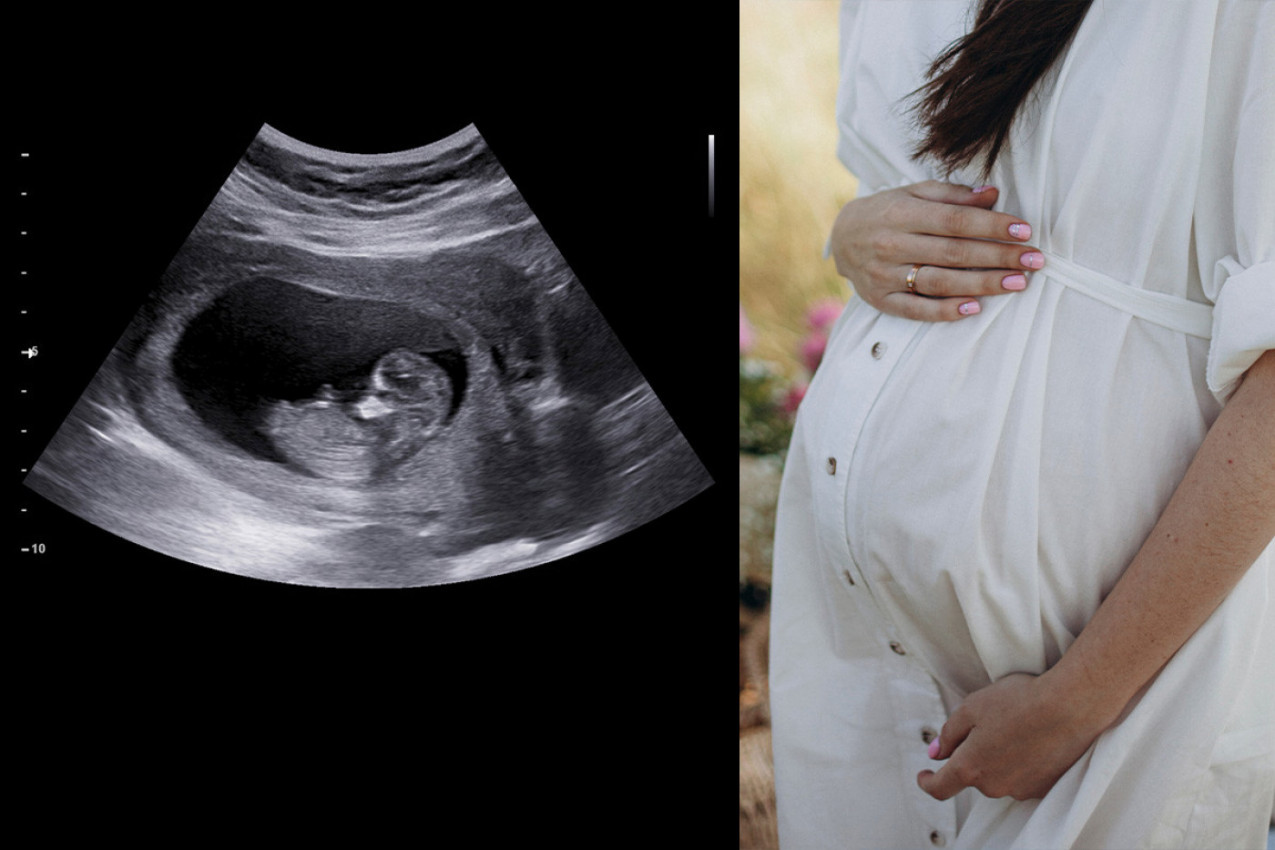

Snimci ultrazvučnih pregleda privukli su pažnju širom sveta, jer su pružili uvid u to kako izgledaju bebe u stomaku kada majka puši. Ovaj fenomen je postao predmet studija istraživača sa Univerziteta u Darhamu i Univerziteta u Lančesteru, koji su odlučili da uporede snimke ultrazvuka beba čije su majke pušile tokom trudnoće sa onima čije majke to nisu radile.

Tokom istraživanja analizirano je 80 ultrazvučnih snimaka beba nastalih između 24. i 36. nedelje trudnoće. Od ukupnog broja snimaka 16 beba imalo je majke koje nisu pušile tokom trudnoće, dok su majke četiri bebe pušile u proseku 14 cigareta dnevno. Rezultati su bili zapanjujući.

Uočeno je da su bebe čije su majke pušile tokom trudnoće pokazivale određene karakteristike na ultrazvučnim snimcima koje nisu imale bebe čije su majke bile nepušači. Ovo je izazvalo zabrinutost među stručnjacima i javnošću, naglašavajući ozbiljne posledice pušenja tokom trudnoće.

Istraživanje sprovedeno na bebama čije su majke pušile tokom trudnoće pokazalo je zanimljive rezultate. Naime, snimci su otkrili da su ove bebe često prekrivale lica i pomerale usta, što ukazuje na značajno veći nivo pokretanja usana u odnosu na prosečnu bebu. Ovo je izazvalo zabrinutost među istraživačima jer sugeriše da nervni sistem beba čije su majke pušile možda nije razvijen na isti način kao kod beba čije su majke izbegavale pušenje tokom trudnoće.

Autorka istraživanja ističe da zaključak izveden iz ovih rezultata upućuje na to da izloženost nikotinu ima veći uticaj na razvoj fetusa, nego izloženost stresu i depresiji.